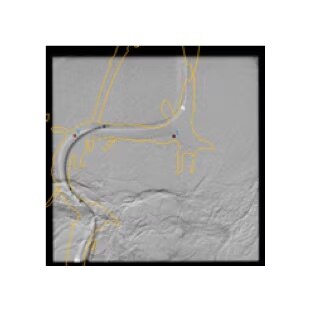

Access

With 3DCT HD and Virtual Dilution visualize the relationship between your device and vessel with robust image quality and without changing your contrast injection protocols. 3,4